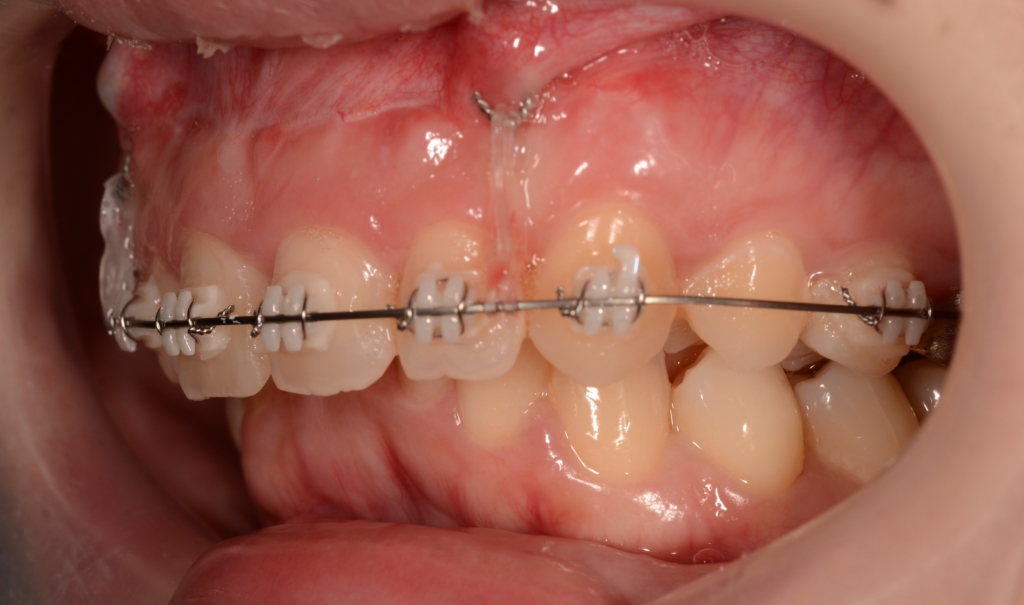

まず、上の歯列だけに矯正装置を付けて、治療を開始します。

マルチブラケットシステム(スタンダードtype)で矯正を開始。

そうこうしているうちに、下の歯列も並んで整ったので、

「上の前歯の圧下」と「下の前歯の後方への移動」を同時進行で行うことにしました。